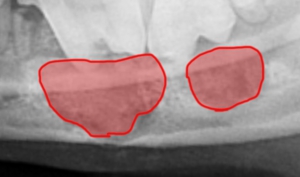

手術日のレントゲンです。赤い部分が骨充填した部位になります。